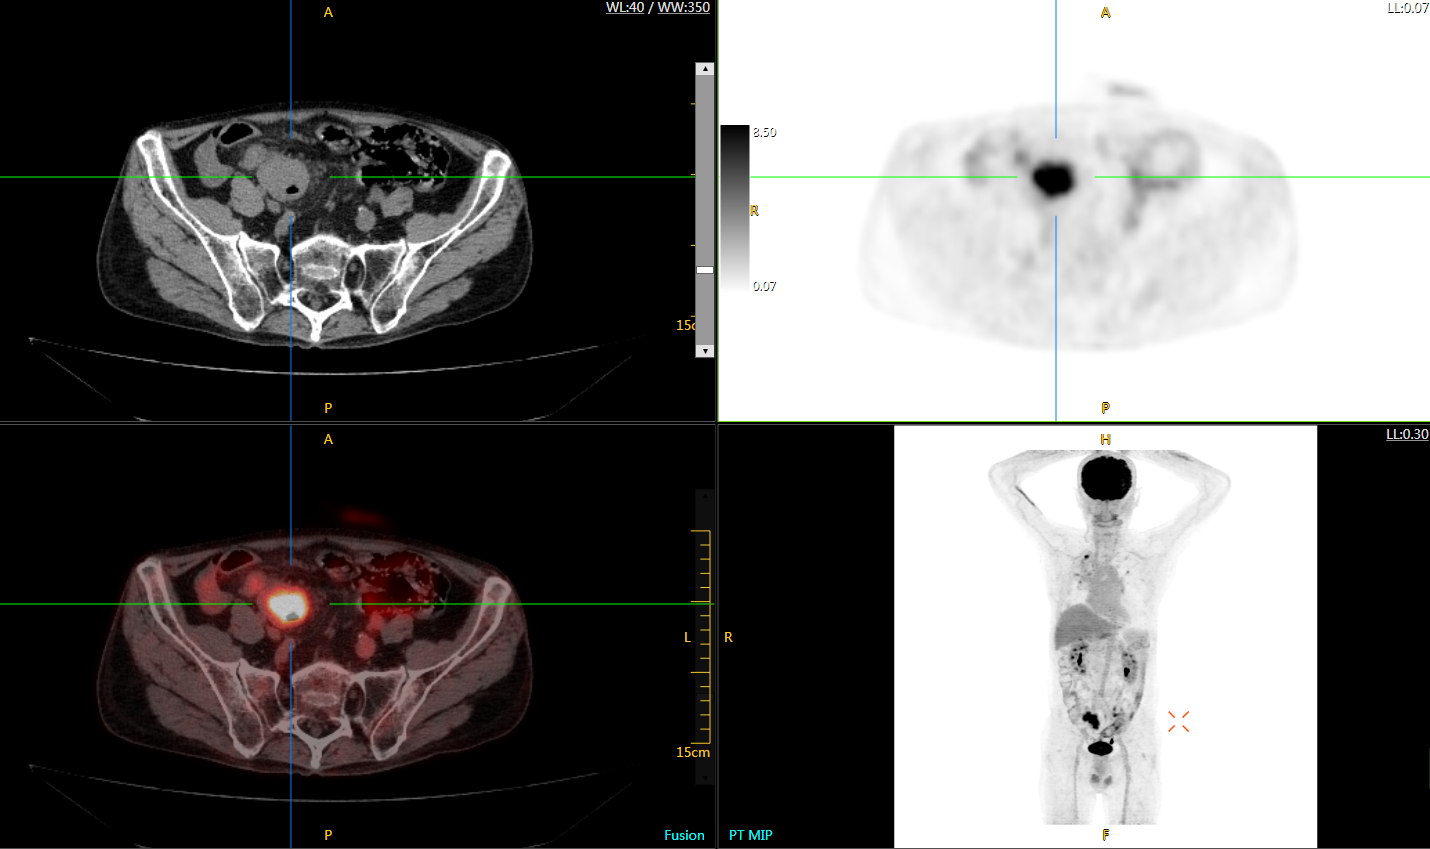

注射總劑量為7.8mCi,14分鐘全身采集時間,在擁有超高靈敏度與超高分辨率的uEXPLORER上,即可得到展示顯示人體諸多精細結(jié)構(gòu)的高清三維圖像。

注射總劑量為7.8mCi,注射后1.6小時,基于uEXPLORER探索者掃描1分鐘的圖像

注射總劑量為0.67 mCi FDG(低于常規(guī)劑量的十分之一),基于uEXPLORER探索者掃描15分鐘的圖像

注射總劑量為6.9mCi,注射后10小時,基于uEXPLORER探索者掃描14分鐘的圖像